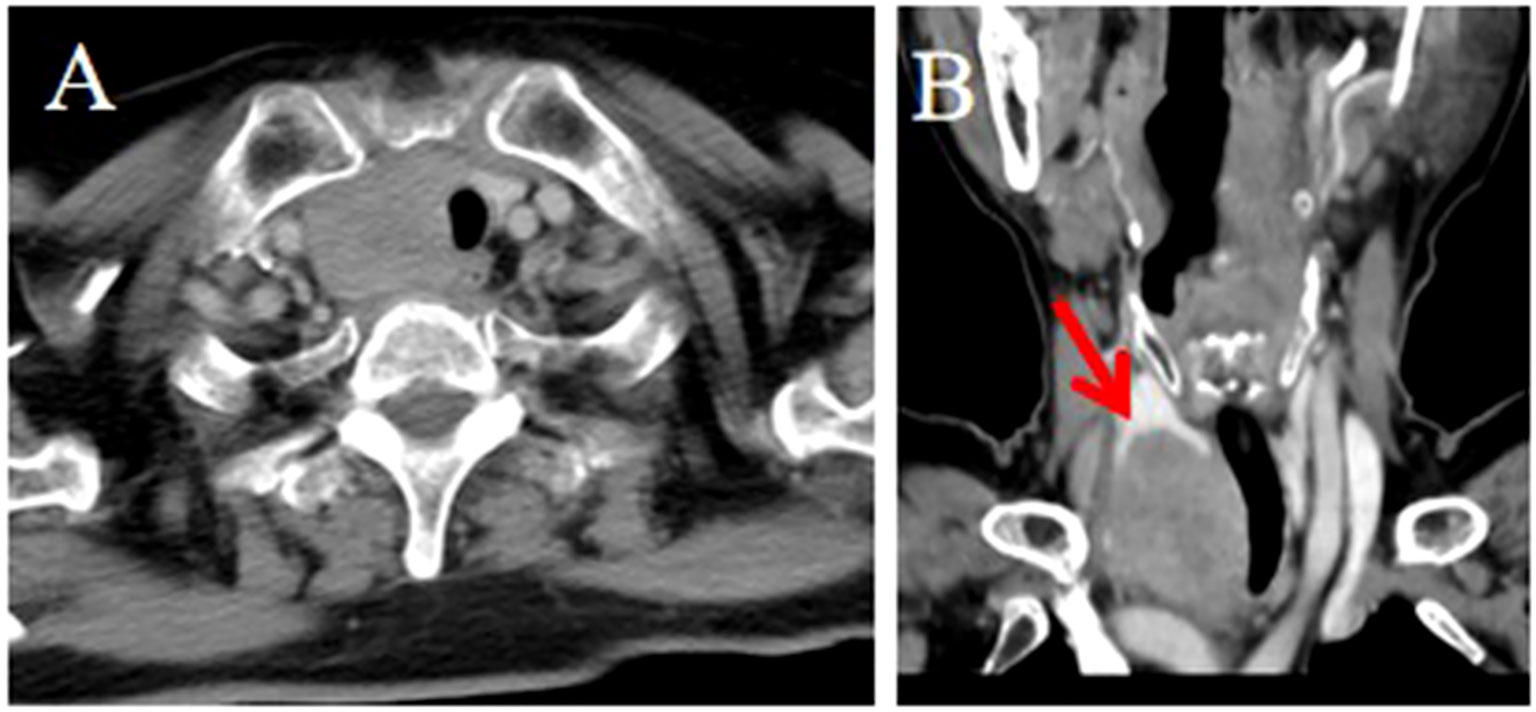

Objective: To summarize the clinical characteristics and imaging features of intrathyroid thymic carcinoma (ITTC), along with diagnostic and therapeutic approaches, to increase awareness of this rare disease. Methods: We retrospectively analyzed 14 patients with ITTC confirmed by core needle biopsy (CNB) and surgery combined with immunohistochemistry. The clinical and imaging findings, treatment, pathological findings and follow-up data of these patients were reviewed. Results: Thirteen patients were newly diagnosed and one relapsed at the original surgical site. All tumors were solitary, mostly located in the lower neck or upper chest, often in the tracheoesophageal groove with or without extension to the thyroid’s lower pole, and approximately two-thirds of patients presented with hoarseness. On CT, most lesions appeared as irregular, low-density soft-tissue masses, with calcification in two cases; contrast-enhanced CT revealed mild heterogeneous or homogeneous enhancement, and over half exhibited an arc-shaped interface with adjacent thyroid tissue. Most tumors were locally advanced, invading muscles, the supraclavicular fossa, tracheoesophageal groove, esophagus, tracheal wall, or mediastinal vessels. The diagnostic accuracy of fine-needle aspiration biopsy (FNAB) was low, whereas core needle biopsy (CNB) combined with immunohistochemistry was reliable. Ten patients underwent radical surgery, of whom three received adjuvant chemoradiotherapy and four adjuvant radiotherapy; four patients received radical chemoradiotherapy, and one received combined therapy including anlotinib, a novel tyrosine kinase inhibitor. The median follow-up was 86 months (range, 25–146), and three surgically treated patients developed local recurrence or pulmonary metastasis. Conclusion: CNB combined with immunohistochemistry is recommended when the characteristic and imaging manifestations suggest a diagnosis of ITTC. Especially for locally advanced cases, imaging-based diagnosis can be useful for analysis and to guide treatment.